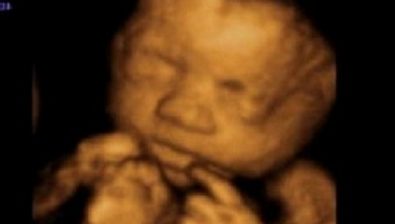

Ultrasound at 38 Weeks

Your baby’s head circumference and waist circumference are around the same size this week.

Your baby is ready for birth but might want to hide out in your uterus for a little bit longer.